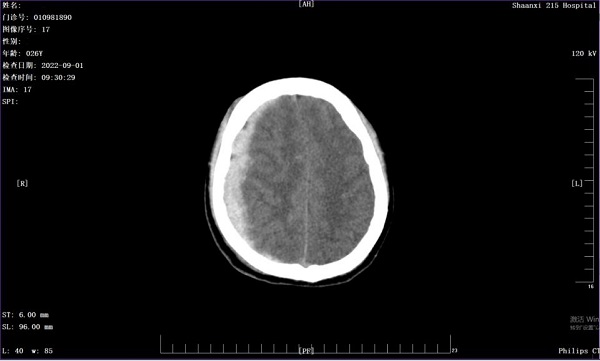

三个月前,26岁的张先生不慎被汽车撞倒,立即陷入昏迷,急诊送入二一五医院救治。入院后CT检查发现,张先生的右侧硬膜下大量出血,诊断为急性右侧硬膜下脑出血伴脑疝形成,病情十分危重。 (入院急诊头颅CT) 对于...